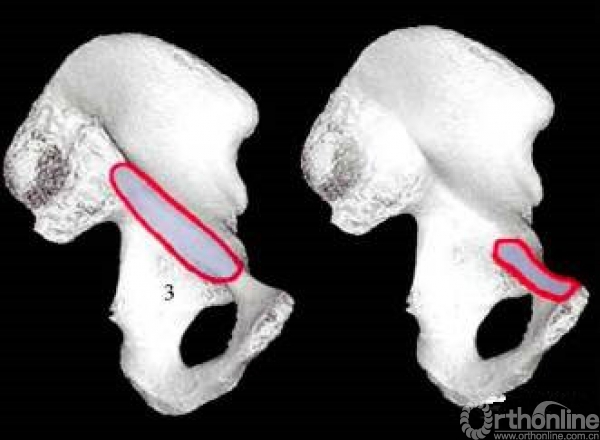

五个手术窗口

窗口3:髂外血管和输精管之间。暴露耻骨支,髂耻隆起,骨盆边缘。

窗口4:输精管内侧。显露耻骨联合。